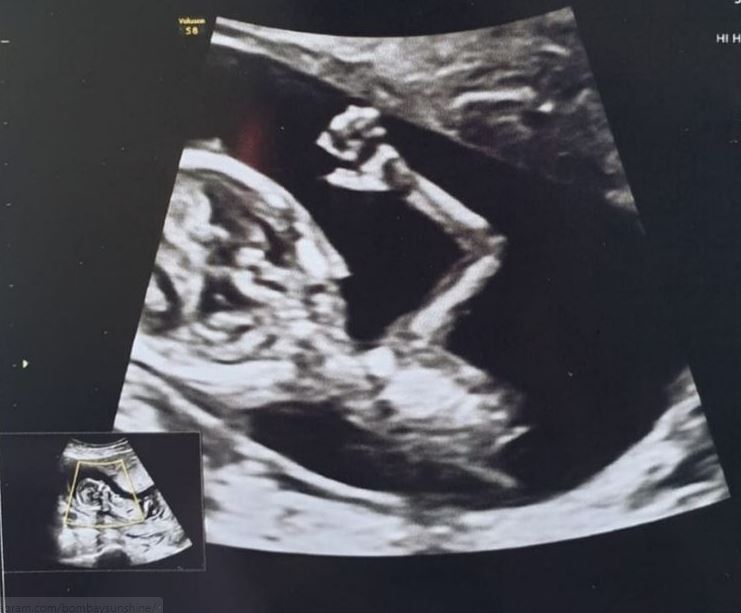

On June 26, 2021, Teejay Sidhu took to her Instagram handle and dropped a special picture from her memory lane that is about her littlest baby girl, Gia Vanessa. The actress shared the picture of Gia Vanessa's first ultrasound when she was thirteen weeks old. The picture is immensely beautiful and memorable. We can spot little Gia's one hand in the picture, and it seemed like she is waving to her parents.

Talking about the same, Teejay penned a note in the caption and stated how she and her husband, Karanvir Bohra had screamed seeing it in real-time. Teejay wrote, "Hi baby girl!! This was almost a year ago.. June 23, 2020.. baby Snow's first ultrasound.. she was thirteen weeks. Was so cute - she waved, we screamed! We couldn't believe it!" Going further in her note, Teejay stated that it was her second pregnancy, yet seeing their child moving inside was an incredible experience for her. She continued, "It was my second pregnancy, but still so unbelievable to see a child moving around inside you!"

Teejay Sidhu also talked about her first pregnancy and revealed the way her twin child used to roll and turn inside. The actress also requested pregnant women to take their ultrasound appointments seriously. She wrote, "In the first pregnancy, the twins rolled and turned etc. but never waved. Dear moms-to-be.. Please savour these ultrasound appointments. Take your time at the doctor's office."

Concluding her note, Teejay Sidhu also advised all the father-to-be out there not to miss any ultrasound check-up, as it's a moment of a lifetime. The actress concluded her note by saying, "Sure, the moments are incredibly special when your baby is newly born, but these UNBORN baby moments are too precious! This is actually the first time you 'meet' your baby. (While you're there, ask for printouts of your #ultrasound. And also take Dad for all these appointments so he doesn't miss out!)"